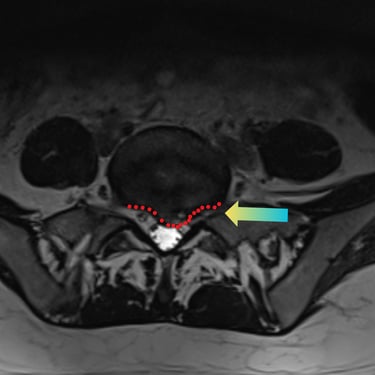

🧠 Listesis L4–L5 con Estenosis Severa: Estabilización con Fijación Transpedicular (FTP) y Fusión Intersomática Transforaminal (TLIF)

La listesis L4–L5 con estenosis severa provoca dolor lumbar e inestabilidad con compresión nerviosa. La fijación transpedicular (FTP) y la fusión intersomática transforaminal (TLIF) permiten descomprimir el canal espinal, estabilizar la columna y mejorar la función de forma segura y progresiva.